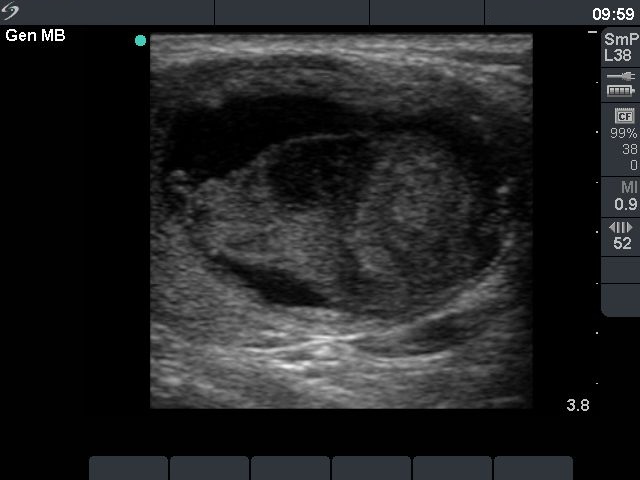

Before sclerotherapy (first row):

Clinical presentation: a 48-year-old man with repeatedly aspirated and recurred thyroid cyst causing complaints.

Palpation: there was a large nodule in the isthmic part of the thyroid.

Ultrasound. The size of the lesion was 38x28x39 mm (width x depth x length).FNAC resulted in a benign lesion.